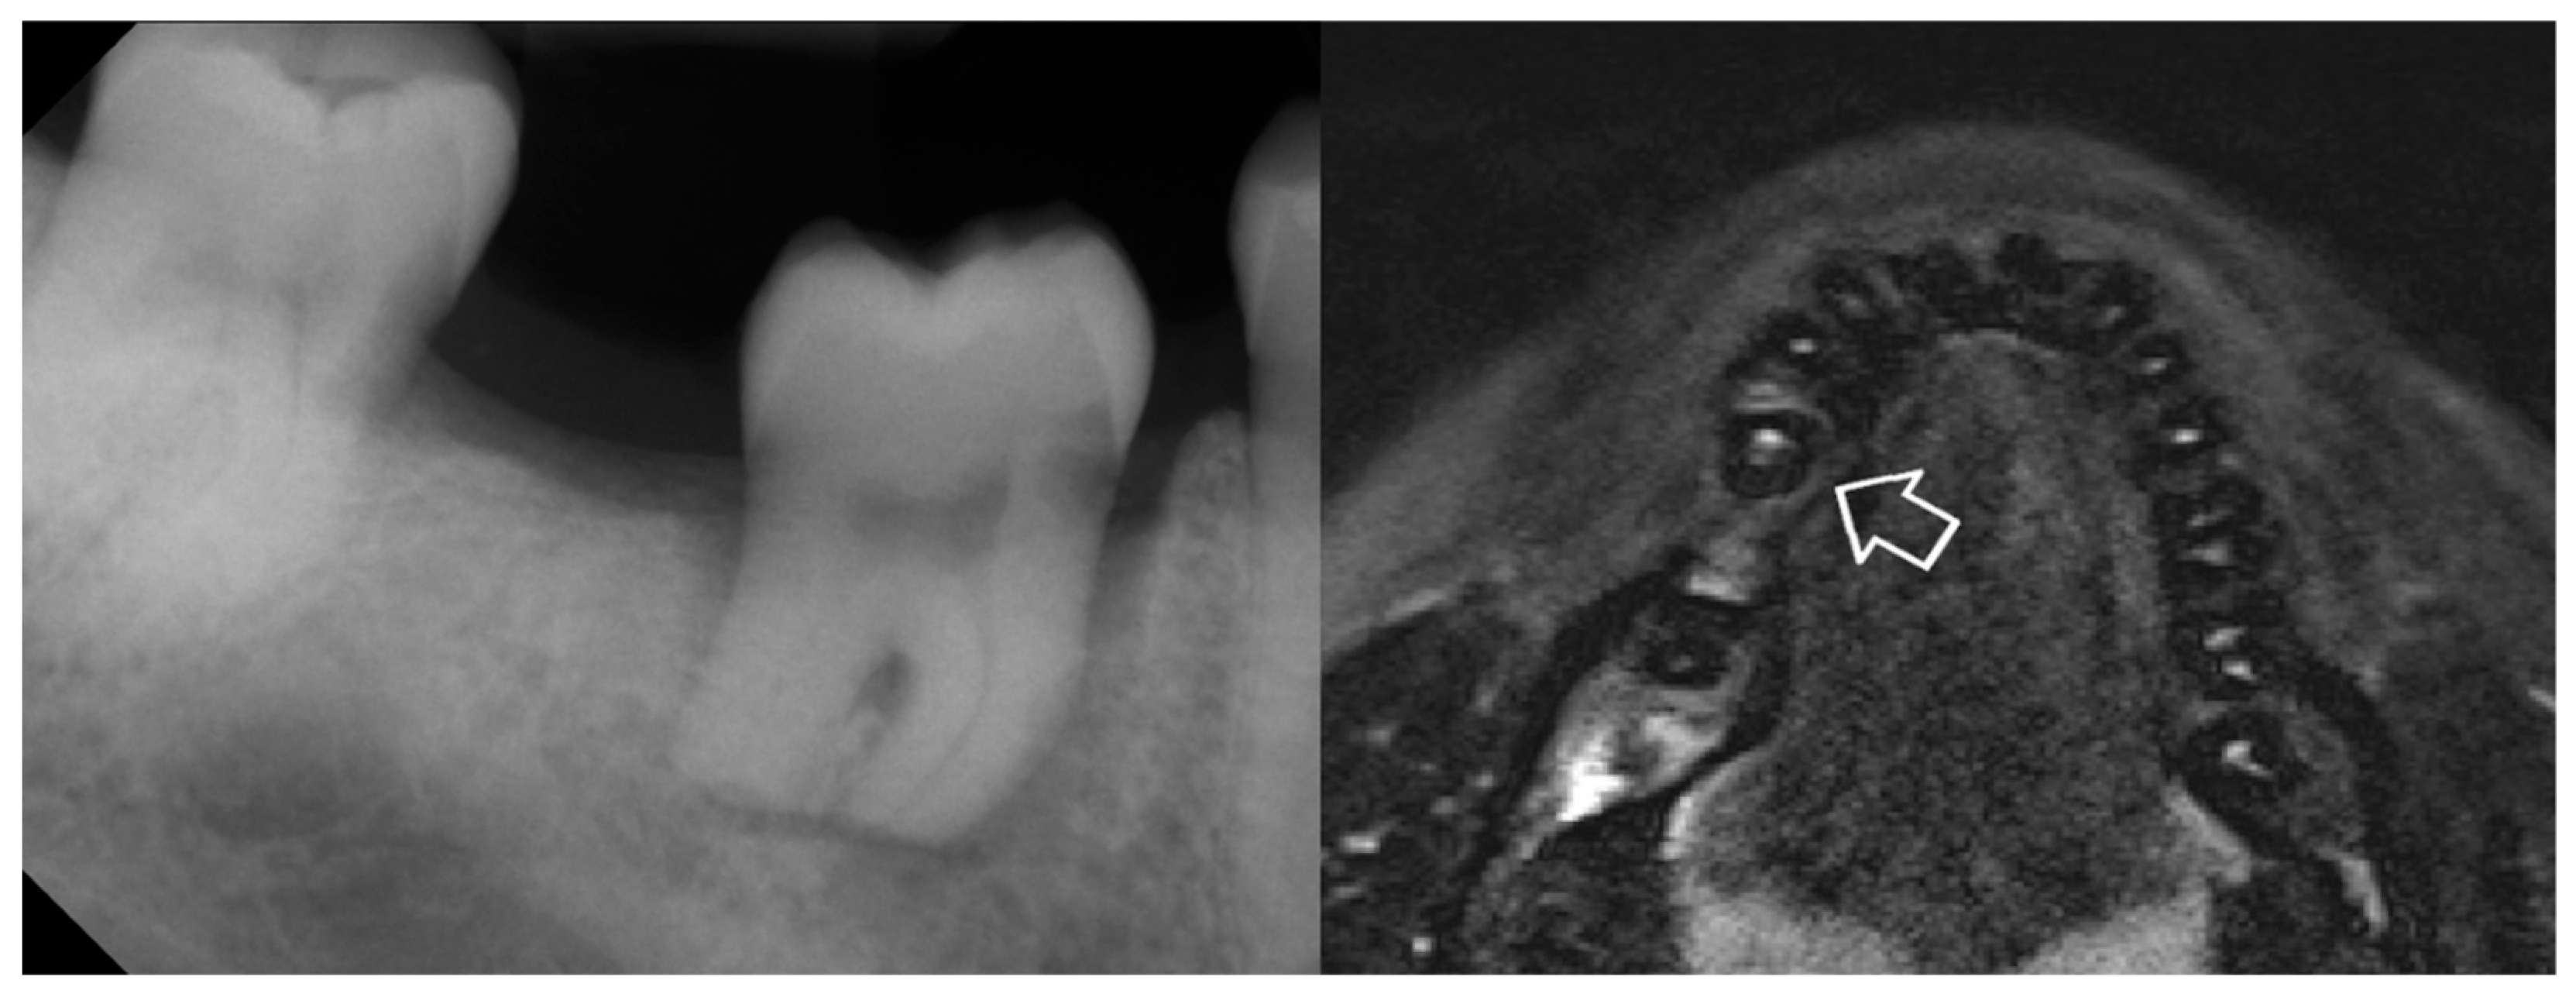

2. Report